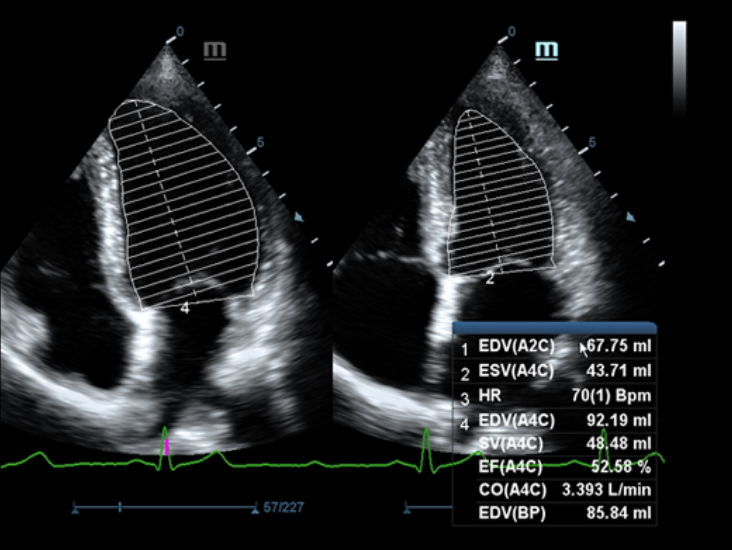

Based on the deep insights of customer needs, the DC-60 ECHO with X-Insight is designed to deliver high efficiency with precision imaging, which is empowered by eXpress Clarity, eXceptional Intelligence and eXceeding Experience.

eXceeding Experience

Experience with high productivity